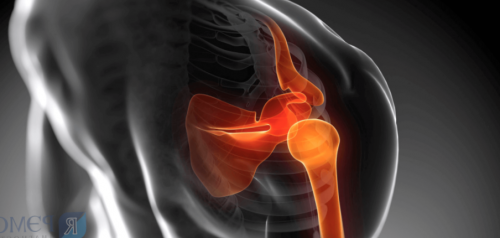

увеличивается с возрастом Другие названия заболевания: плечелопаточный периартроз, плечевая артропатия, синдром «замороженного плеча», «болезненное плечо», «шейно-плечевой синдром», «плечо пятидесятилетних», говорящие о боли Плечелопаточный периартрит — поражение околосуставных мягких

Определение болезни. Причины заболевания

Патогенез плечелопаточного периартрита